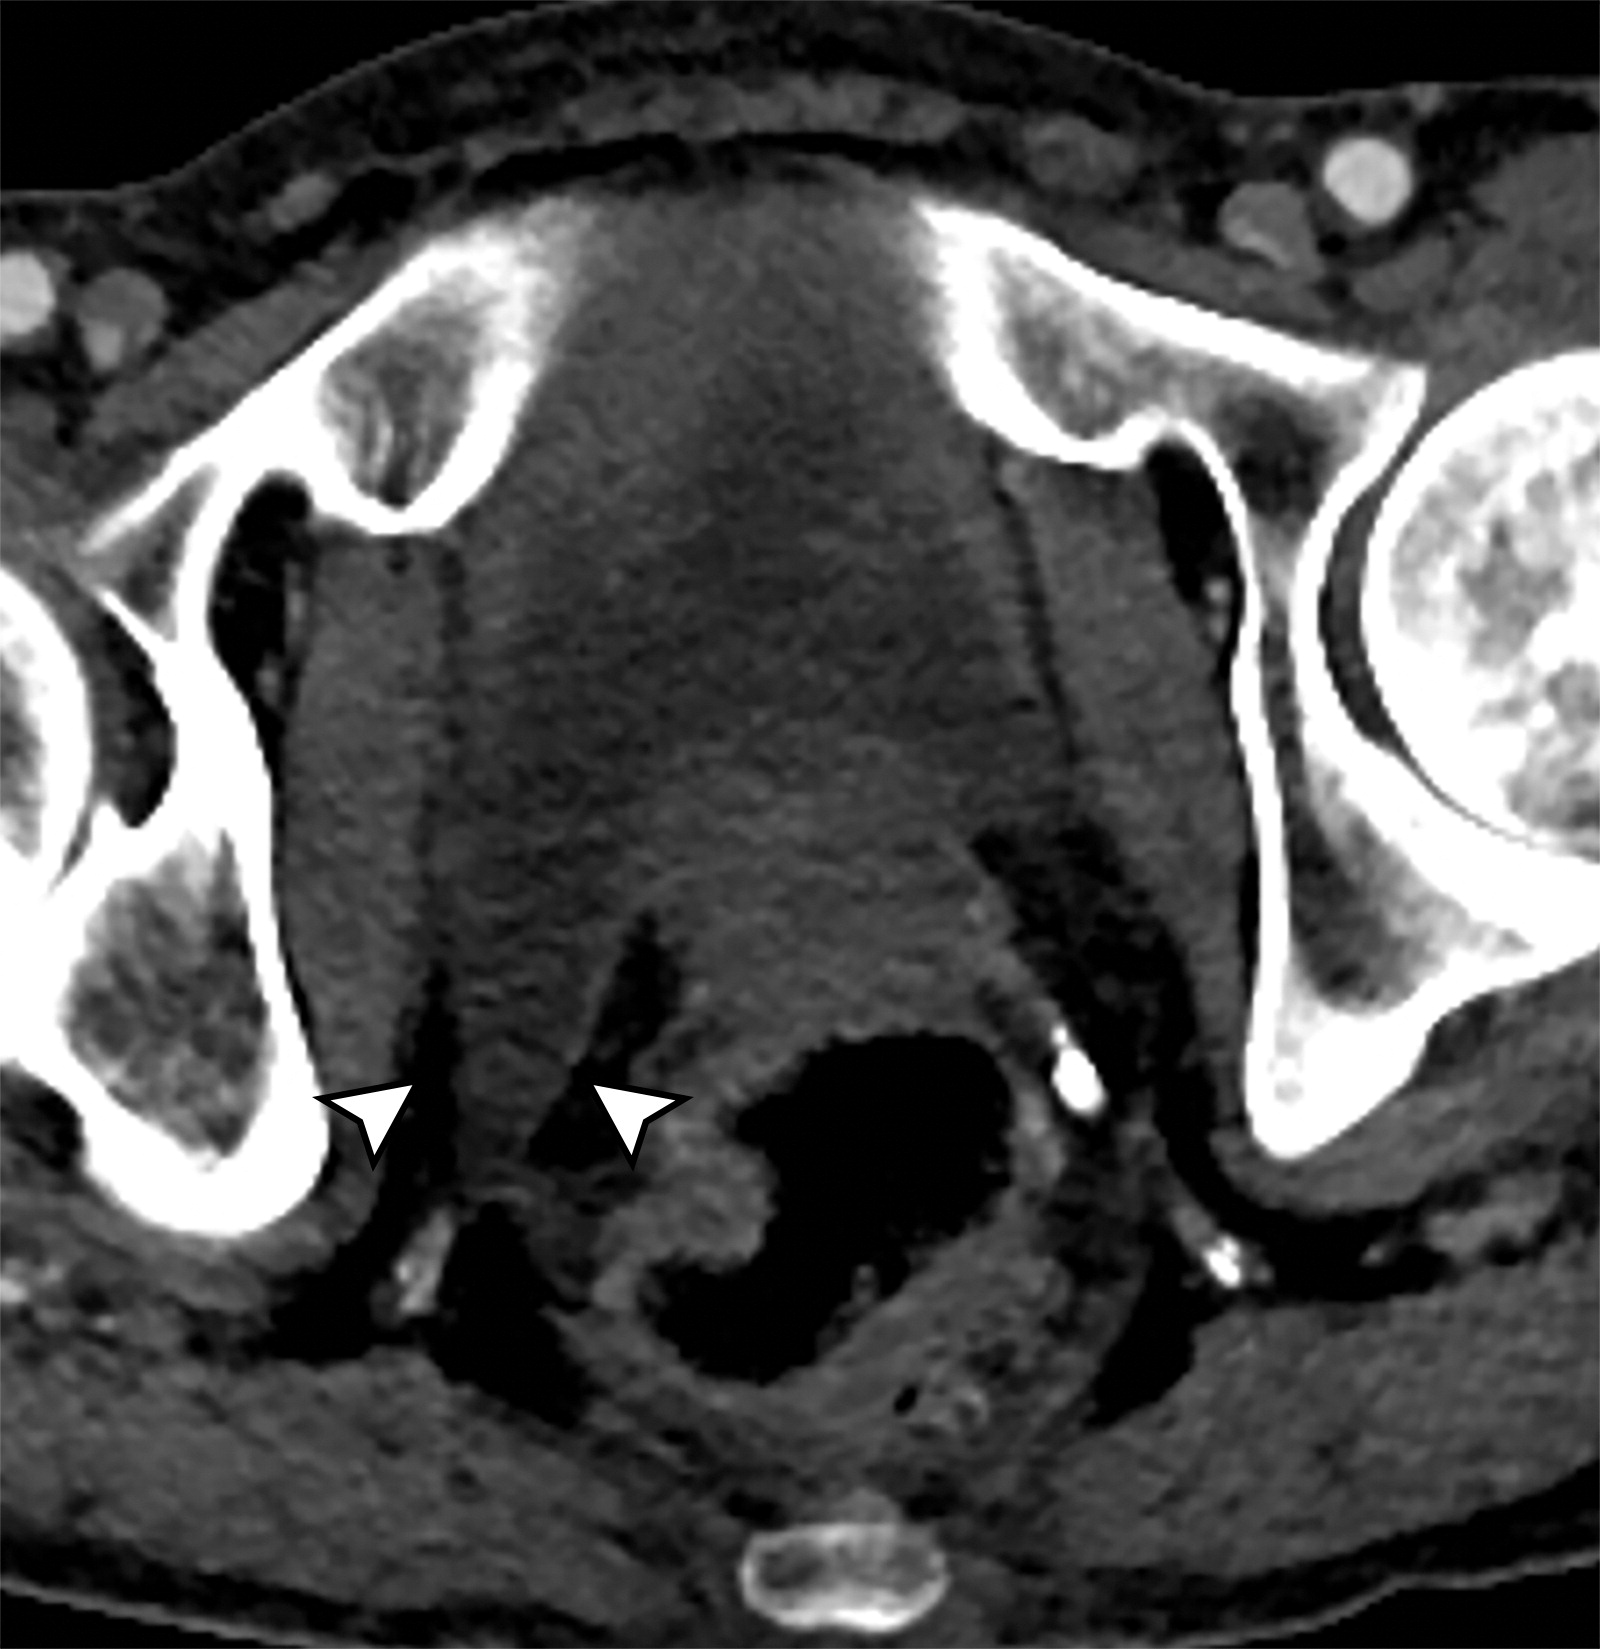

45d202b8c9b68c9a5a2f56b9e29f9039.jpeg709dc23c4aabdb61c1873e30f3ca4c92.jpeg

尿道吊带。

白色长箭头示尿道吊带的正常位置,正常的尿道吊带是薄的T2WI低信号影,向外延伸至闭孔。